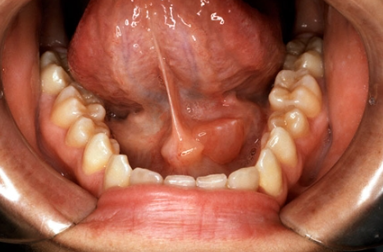

③ 타석증(침샘 결석)

침샘관 안에 돌(타석)이 생겨 침이 제대로 배출되지 않으면 반복적인 염증을 초래합니다. 타석 크기에 따라 저절로 배출되기도 하지만, 크거나 만성적인 경우 내시경적 제거 또는 수술이 필요할 수 있습니다.

의료기관에서는 영상 검사를 통해 침샘 상태를 확인하고, 필요한 경우 수술적 제거, 침샘내시경, 약물 치료 계획을 세웁니다.